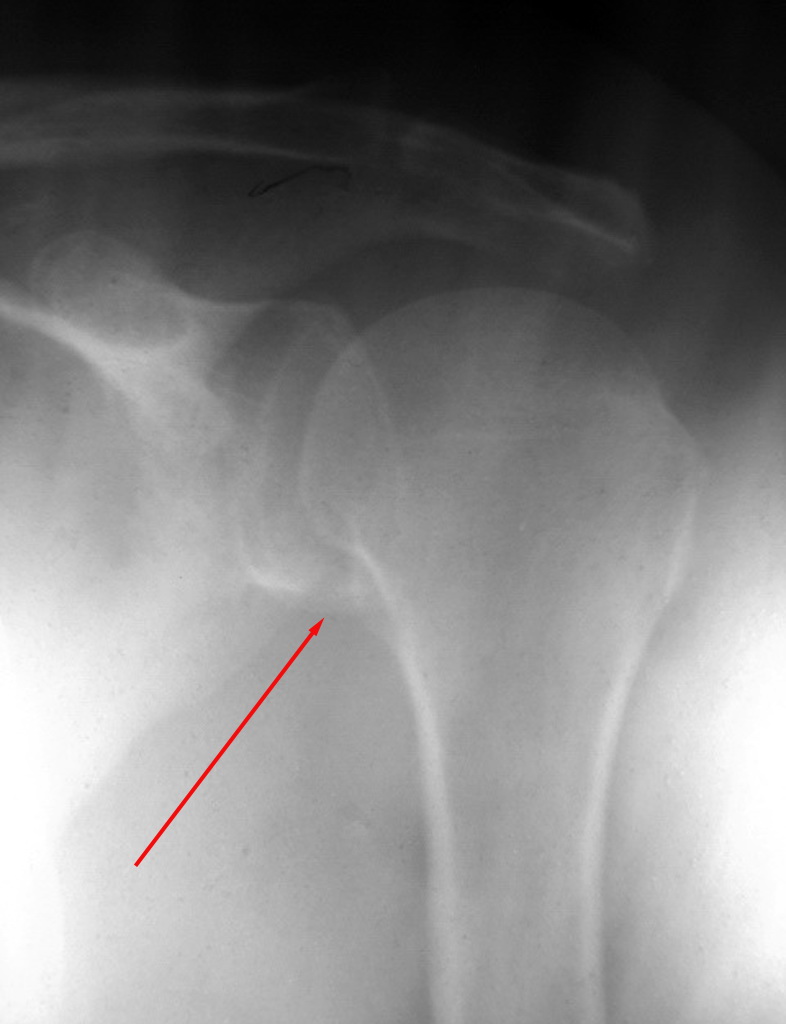

女.56,颈部及肩部疼痛半年,椎弓根及肩关节正常吗

未见异常。

未见异常! 从颈椎斜位观察:应为颈椎间盘病变

颈部看不清,肩部没问题。

颈椎,肩关节未见明显异常改变。颈椎正侧位呢?

体位不正,颈椎有退行性变